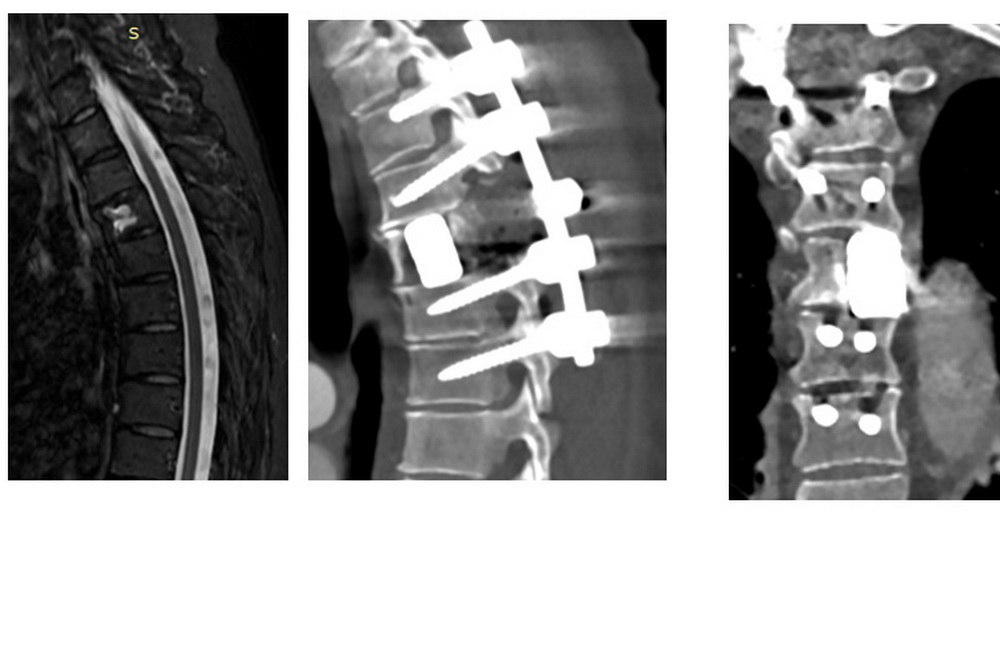

В НИИТО ей поставили диагноз «аневризматическая костная киста Th4 позвонка». Врачи объяснили, что такой вариант опухоли встречается в разных отделах скелета, в частности — в позвоночнике.

«Существуют определённые современные подходы к лечению этого вида патологии. Всё зависит от её локализации и степени агрессивности. У нашей пациентки агрессивное новообразование. Опухоль разрушила верхнюю замыкательную пластинку и переднюю стенку тела 4-го грудного позвонка. Был высокий риск патологического перелома, что могло привести к серьёзным последствиям», — пояснил хирург-вертебролог Алексей Ластевский.

«Нам пришлось удалить не только саму опухоль, но и часть здоровой костной ткани вокруг. Далее мы провели реконструкцию передней колонны позвоночника титановым имплантом и после этого выполнили дополнительную заднюю стабилизацию специальной винтовой конструкцией», — рассказал Алексей Ластевский.